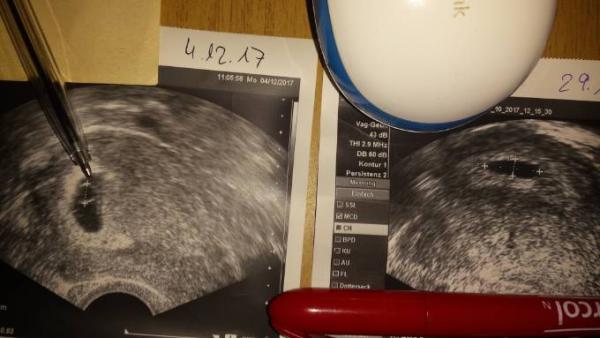

Hallo Ich bin total verzweifelt Mein Fa sagte mir heute dass es keine intakte Schwangerschaft sei. Erst hieß es es wäre ein Windei Hat jemand Erfahrung und kann mir weiterhelfen? Was ist denn das auf der rechten Seite neben dem dottersack wo die Mine vom Stift ist??????

Bild zu FG ja oder nein - Schwanger - wer noch? Rund um die Schwangerschaft

Ich erkenne zumindest, dass sich deine Fruchthöhle vergrößert hat und auf dem einen Bild ein schöner Dottersack vorhanden ist. Meine letzten beiden Babys waren Eckenhocker und hat man erst in der 8 SSW gesehen. Wünsche Dir alles Gute, dass es sich doch noch positiv entwickelt.

Hallo erstmal und fühl dich gedrückt. Es sieht so nach der 4/5 ssw aus. In welcher bist du denn? Es kann bei jeder Frau unterschiedlich die Entwicklung sein. Manchmal hilft es bis zum nächsten US zu warten und man sieht auf einmal alles.

Bei einem Windei ist die Fruchthöhle eigentlich komplett leer. Mein US Bild sah an 5+6 genauso aus. Wie weit bist du denn?

Hallo, also ich kann - wie schon letzte Woche bei deinen Bildern - leider nach wie vor nichts erkennen. Du bist heute ja schon 7+1, da müsste meiner bescheidenen Meinung nach schon mehr zu sehen sein...

Hab eben erst den Post von letzter Woche gesehen. Für 7+ sieht man tatsächlich zu wenig. Da war bei mir schon ein 1cm grosser Embryo mit Herzschlag. Wurde dein HCG kontrolliert?

Mir hat mal eine Hebamme gesagt wo ein Dottersack ist da ist auch ein Embrio und wenn er noch so klein ist. Wenn du keine Schmerzen hast würde ich auf jeden Fall weiter abwarten. Es kann sich alles so schnell ändern. Finde heutzutage wird alles viel zu schnell abgebrochen es schadet doch keinem zu Warten. Dann hast du wenigstens das Gefühl alles getan zu haben falls es doch nichts wird. Ich hatte 2014 übrigens ein Windei da war die Fruchthülle komplett leer da war überhaupt nichts drin. Drücke dir die Daumen

Ich bin auch für abwarten,es kann doch sein das der es später war,was positiv wäre ist das die Fruchthülle immer noch schön rund ist und nicht "schrumpelig",ich würde immer abwarten,ich hatte drei Eckenhocker